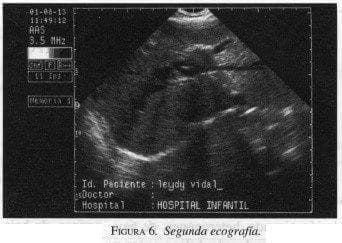

Dos años después la US (figura 6) y TAC (figura 7) de control demostraron regresión completa del tumor, persistiendo la dilatación moderada de la vía biliar; además se presentó salida accidental del tubo sinfín. A la fecha la paciente se encuentra asintomática.